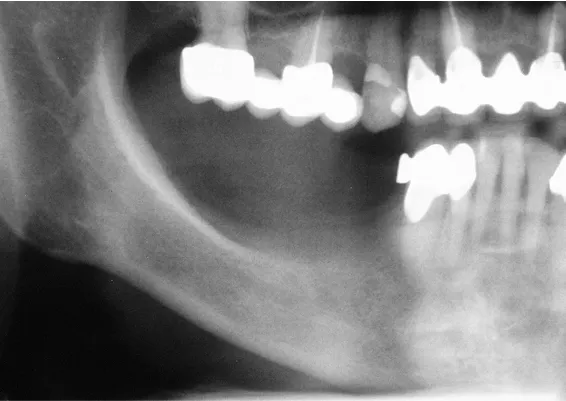

TRANSPOZYCJA NERWÓW ZĘBODOŁOWYCH DOLNYCH – IANT

Ta szczególna metoda używana jest w obszarze dolnego łuku zębowego w sytuacji braku dostatecznej ilości kości na wysokość. Metoda stosowana jest w sytuacji rozległych zaników kostnych w bocznych odcinkach żuchwy, w której wprowadzenie implantów groziłoby uszkodzeniem gałązek nerwowych nerwów zębodołowych dolnych. Gałązki nerwowe biegną wraz z naczyniami krwionoś-nymi we wspólnej pochewce w kanałach kostnych, umieszczonych symetrycznie po obu stronach w trzonach żuchwy.

Technika polega na chirurgicznym ich przemieszczeniu, a przez to stworzeniu bezpiecznego miejsca dla wszczepienia implantów o odpowiednej długości, co gwarantuje ich stabilną pozycję. Stosuje się ją wraz z zabiegiem rekonstrukcji kostnej przy użyciu biomateriałów w formie granulatu i membran.

Zabieg ten stosowany jest rzadko, jako alternatywa rozległych regeneracji kostnych. Wybierany bywa jako alternatywa operacyjna tylko w sytuacji, gdy konwencjonalne metody odbudowy kostnej są niewystarczające lub generują ryzyko braku skutecznej odbudowy kostnej celem wszczepienia implantu.